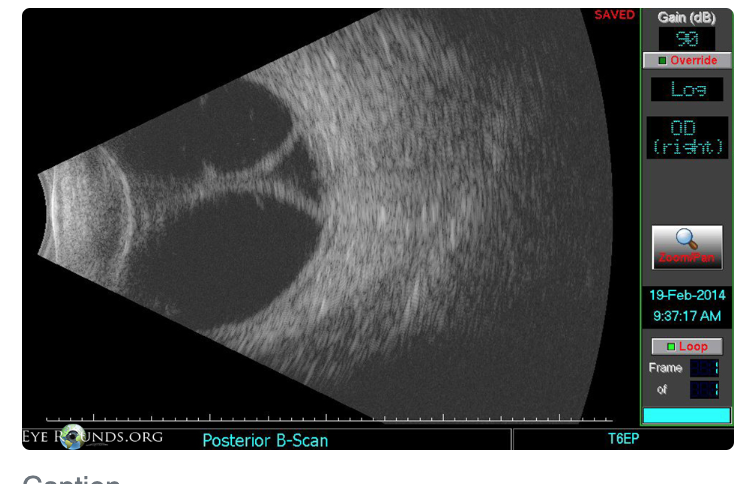

B-scan

Pathological Myopia/Myopic Degeneration?

Posterior staphyloma (outpouching of post seg as white circles = visible choroid)